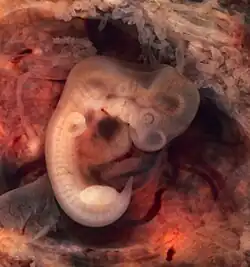

Desenvolvimento embrionário

Nos seres humanos, a embriogénese, ou período embrionário, tem início com a fecundação e prolonga-se até ao início do período fetal. Após a fecundação, o zigoto desloca-se lentamente ao longo da trompa de Falópio em direção ao útero. Ao longo desta viagem de mais de uma semana, o zigoto divide-se em células idênticas. Esta divisão celular tem início aproximadamente entre 24 a 36 horas após a fecundação. Ao fim do 4º dia de divisão celular, o zigoto dá origem a uma esfera sólida de 16 ou 32 células denominada mórula. Ao chegar ao útero, cinco dias após a fecundação, esta esfera apresenta-se oca e tem entre 50 e 100 células. Nesta fase passa a ser denominada blastócito, demorando cerca de seis dias até nidificar na parede uterina. O revestimento de proteínas do blastócito dissolve-se, o que permite às suas células trofoblásticas entrar em contacto e aderir às células endometriais da parede uterina. O embrião une-se com o endométrio através de um processo denominado nidação, que ocorre oito a dez dias após a ovulação. Após alguns dias, forma-se o celoma extra-embrionário que se tornará na cavidade coriónica, a qual irá conter o embrião, o líquido amniótico e o cordão umbilical. Desenvolve-se também a cavidade amniótica entre o citotrofoblasto e a massa de células interna. Desenvolve-se também a placa pré-cordal, que indica o futuro local da boca e da região cranial. Nesta fase, o embrião cresce rapidamente e começam a tomar forma as principais características externas. Este processo, denominado diferenciação celular, produz os diferentes tipos de células do organismo.[41][42][43]

À sexta semana de idade gestacional (quarta semana de idade embrionária), o embrião mede cerca de 4 mm de comprimento e começa-se a curvar em forma de C. O coração desenvolve-se e começa a bater a um ritmo regular, aparece o septo primário e formam-se as cavidades que irão dar origem às estruturas da face e do pescoço, sendo já visível o início da formação dos braços e de uma cauda. O tubo neural encerra, aparecem os primeiros traços do pulmão e do fígado, aparecem ainda as estruturas que formarão o pâncreas e o baço e rompe-se a membrana bucofaríngea que formará boca. Na medula espinal, começa-se a diferenciar o corno anterior e posterior. Durante a sétima semana de idade gestacional (quinta semana de idade embrionária) o embrião mede cerca de 9 mm de comprimento. Nesta semana, começam-se a desenvolver as estruturas que formarão os olhos e o nariz e os brotos das pernas e das mãos. O cérebro divide-se em cinco vesículas, incluindo o telencéfalo primitivo e inicia-se a diferenciação do estômago. Existe já uma circulação sanguínea primitiva entre os vasos que ligam a vesícula vitelina e as vilosidades coriónicas. Inicia-se ainda o desenvolvimento do metanefro, precursor dos rins.[44]

Durante a oitava semana de idade gestacional (sexta semana de idade embrionária) o embrião mede aproximadamente 13 mm de comprimento. Começam-se a formar os pulmões, o sistema linfático e os órgãos genitais externos, sendo também visível a crista gonadal. Os braços e as pernas aumentam de comprimento, sendo agora visíveis as áreas dos pés e das mãos, as quais já têm dedos mas que ainda estão unidos.[44] Durante a nona semana de idade gestacional (sétima semana de idade embrionária) o embrião mede cerca de 18 mm de comprimento, estando já em processo de formação todos os órgãos essenciais. É possível ouvir o som do batimento cardíaco através de doppler e pode ser possível observar movimentos espontâneos dos membros através de ecografia. Começam-se a formar os folículos pilosos e os mamilos, são visíveis os cotovelos e os dedos dos pés e o ducto vitelino é geralmente encerrado. Ao fim da nona semana, decorreram 49 dias desde a fecundação e 63 dias desde o primeiro dia do último período menstrual.[44] Ao longo da décima semana de gestação (oitava semana de idade embrionária), as pálpebras estão mais desenvolvidas e começam-se a fechar e as orelhas e as características faciais tornam-se mais distintas.[32]